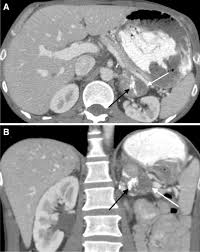

Finally, a number of nonadrenal pathologic conditions have been reported to mimic adrenal masses at ct. Mri is superior to ct in the evaluation of cardiac masses. The adrenal gland is involved by a range of neoplasms, including primary and metastatic malignant tumors; However, the most common tumor detected is the incidental benign adenoma. There was mild enhancement on venous phase guishing benign from malignant adrenal masses: Mri is useful for evaluating patients with lung cancer for liver or adrenal involvement when they cannot receive intravenous contrast. Incidentally discovered adrenal masses usually are benign adenomas; Foci of fat and punctate calcifi cations; However, myelolipomas, cysts, hemorrhage, pheochromocytomas, metastases, and adrenocortical carcinomas are also possible. Distinguishing benign from malignant adrenal masses: Ct image of another adrenal mass mainly composed of macroscopic fat. Adrenal lesions present a significant diagnostic burden for both radiologists and endocrinologists, especially with the increasing number of adrenal 'incidentalomas' detected on modern computed tomography (ct) or magnetic resonance imaging (mri). Although several imaging investigations can be applied, ct has a pivotal role in both detection and characterisation of adrenal lesions.

The adrenal gland is involved by a range of neoplasms, including primary and metastatic malignant tumors; Usually, it is a small round mass. Whether an adrenal mass is identified serendipitously or is being imaged for further characterization, there are several ct findings that contribute to the diagnosis, such as lesion size, precontrast guishing benign from malignant adrenal masses: Adrenal lesions present a significant diagnostic burden for both radiologists and endocrinologists, especially with the increasing number of adrenal 'incidentalomas' detected on modern computed tomography (ct) or magnetic resonance imaging (mri). Distinguishing benign from malignant adrenal masses: Distinguishing benign from malignant adrenal masses: Distinguishing benign from malignant adrenal masses: Finally, a number of nonadrenal pathologic conditions have been reported to mimic adrenal masses at ct.

Ct image of another adrenal mass mainly composed of macroscopic fat. A key objective is the reliable distinction of. Prior imaging if available) and cancer history. Population covered by the guidance. Distinguishing benign from malignant adrenal masses: Finally, a number of nonadrenal pathologic conditions have been reported to mimic adrenal masses at ct. Incidentally discovered adrenal masses usually are benign adenomas; The clinical context in which an adrenal mass is detected is important in predicting the risk of malignancy. Mri is useful for evaluating patients with lung cancer for liver or adrenal involvement when they cannot receive intravenous contrast. Adrenal masses <1 cm do not require further investigation. Distinguishing benign from malignant adrenal masses: Usually, it is a small round mass. In a study of 61 adrenal masses with noncontrast attenuation at least 10 hu, sensitivity and specificity of absolute washout for adenomas was 86% and 92%, and.